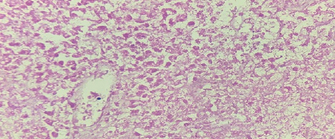

Oncocytoma, with a solid growth pattern, composed of polygonal cells, with dense granular eosinophilic cytoplasm (Courtesy Dr. V. Penopoulos)